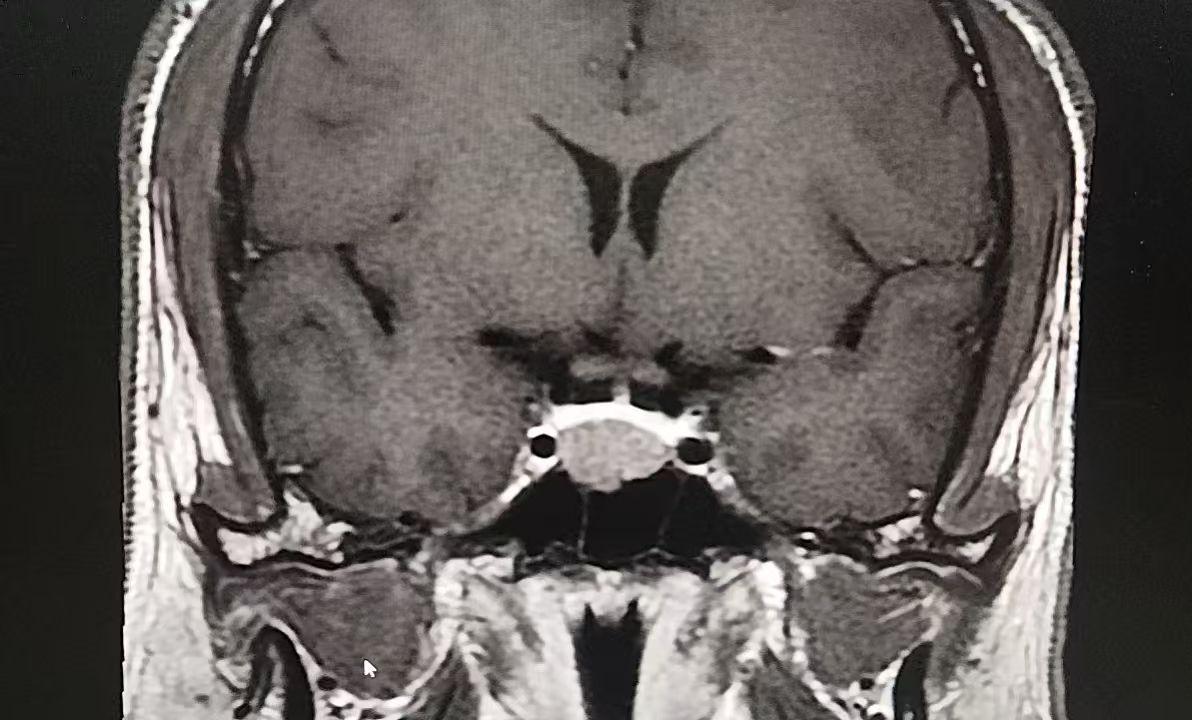

颅脑磁共振结果出来时,肖先生才知道,困扰他两年的“小毛病”,根源在颅内——鞍区占位。神经外科团队结合患者病史、体征及生长激素检验结果,最终确诊其为“垂体生长激素瘤”。

垂体瘤是起源于垂体前叶的常见颅内肿瘤,肖先生的肿瘤已侵犯鞍底硬膜。若不及时干预,不仅会持续加重头痛、内分泌紊乱,还可能引发视力视野损害等严重并发症。